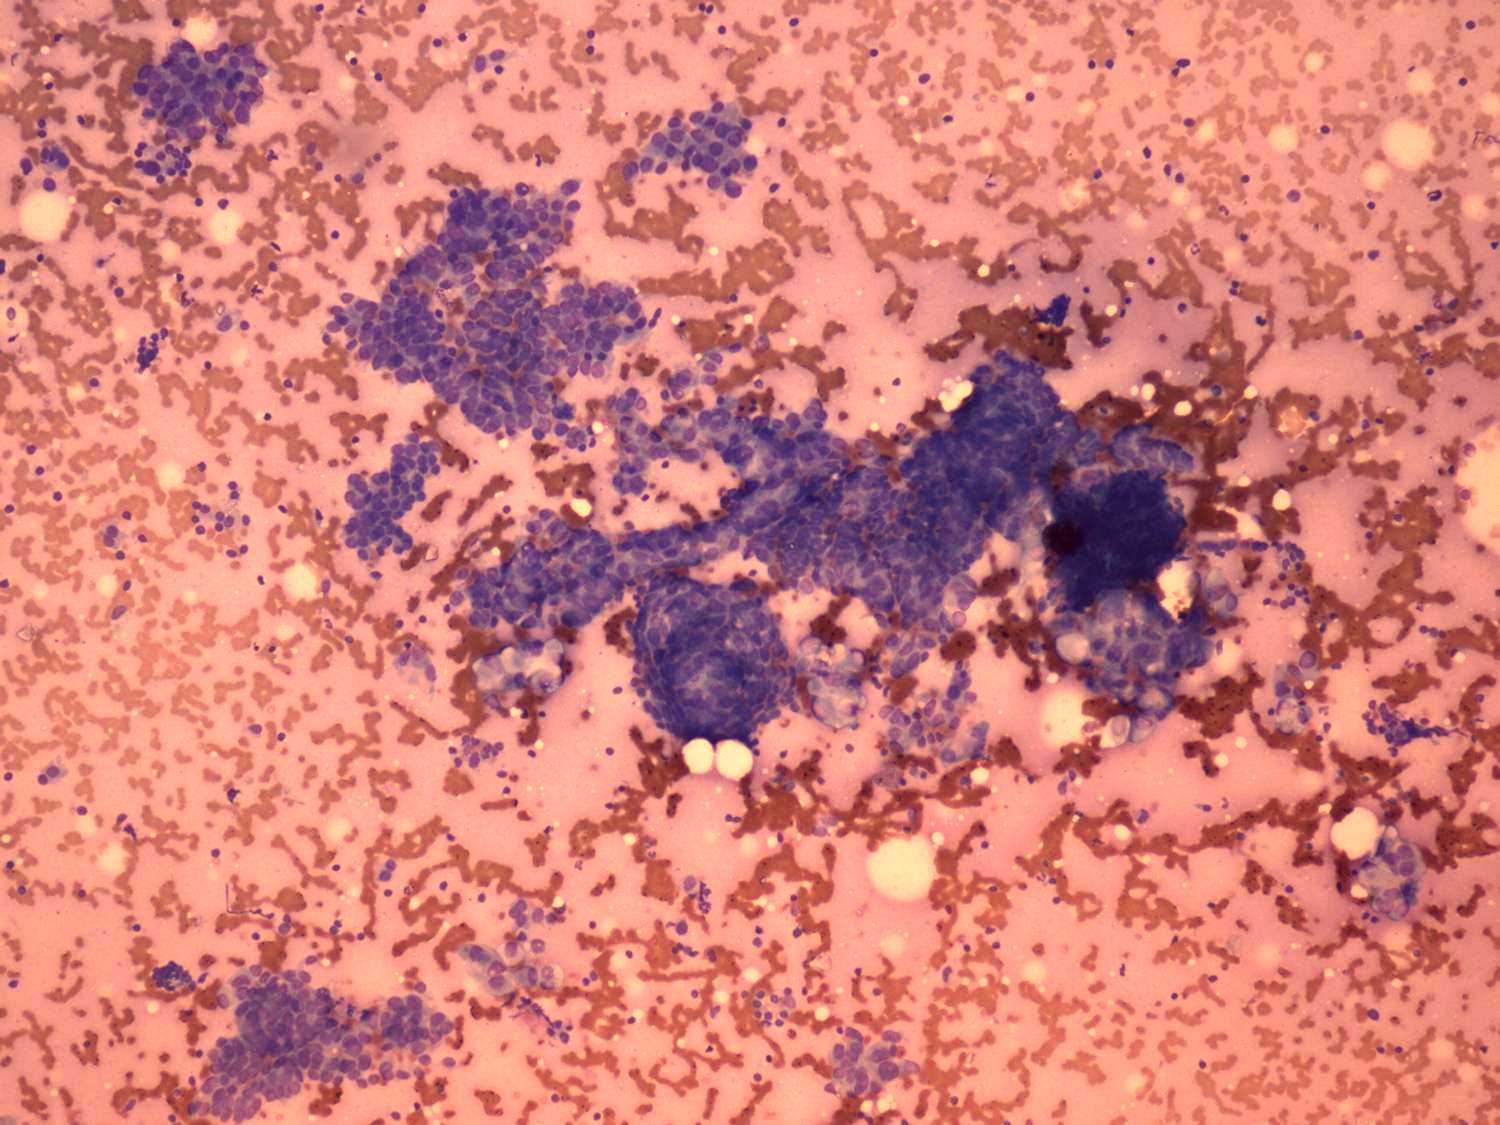

Wright-Giemsa staining, 100x.   There is no colloid in the background. Papillary cell clusters are presented.